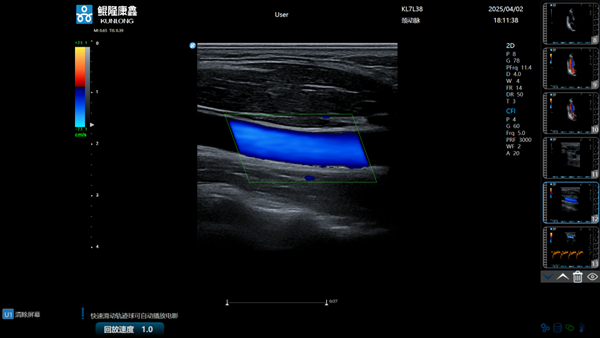

克日,,,,,,,在包河区中国视界园区,,,,,,,安徽鲲隆康鑫医疗科技有限公司(简称“鲲隆康鑫”)生产的“彩色多普勒超声诊断仪”正式获批量产,,,,,,,这是安徽本土企业自主研爆发产的首款彩色超声影像诊断装备,,,,,,,标记着安徽省在高性能医学影像装备领域实现重大突破。。。。

据悉,,,,,,,鲲隆康鑫自主研发的彩色多普勒超声诊断仪是一款集成了先进超声成像手艺的立异型医疗装备,,,,,,,该产品依附128通道数字波束形成手艺,,,,,,,实现黑点追踪、组织多普勒成像等多种高级成像功效,,,,,,,具有图像清晰、功效周全、操作便捷等特点,,,,,,,在要害手艺指标上已靠近国际主流水平,,,,,,,可用于腹部、心脏、血管、妇产等临床诊断,,,,,,,为临床医生提供更精准、更高效的诊断依据。。。。

作为“包河智造”的本土代表性效果,,,,,,,“彩色多普勒超声诊断仪”的量产上市不但填补了省内超声影像诊断装备领域的手艺空缺,,,,,,,更以国际主流水平的成像性能、仅为入口产品60%-70%的价钱,,,,,,,有望突破入口品牌恒久垄断的时势,,,,,,,发动省内细密制造、电子信息等相关工业链企业的协同生长。。。。